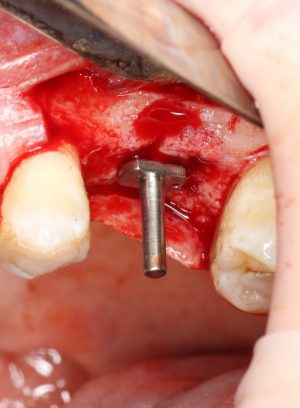

После этого можно еще раз (последний, кстати), проверить направление и ангуляцию оси будущего имплантата. Всё тем же вышеозначенным пином:

Если бы мы хотели поставить имплантат диаметром 4.5 мм, то далее мы перешли бы к кортикальной конической фрезе. Однако ж, я посчитал, имплантат диаметром 5.0 мм в данной клинической ситуации будет более надежным и органичным, поэтому мы продолжаем подготовку лунки. И следующая используемая фреза — 3.2/3.7 — то же самое. что и предыдущая, с направляющей 3.2 мм: